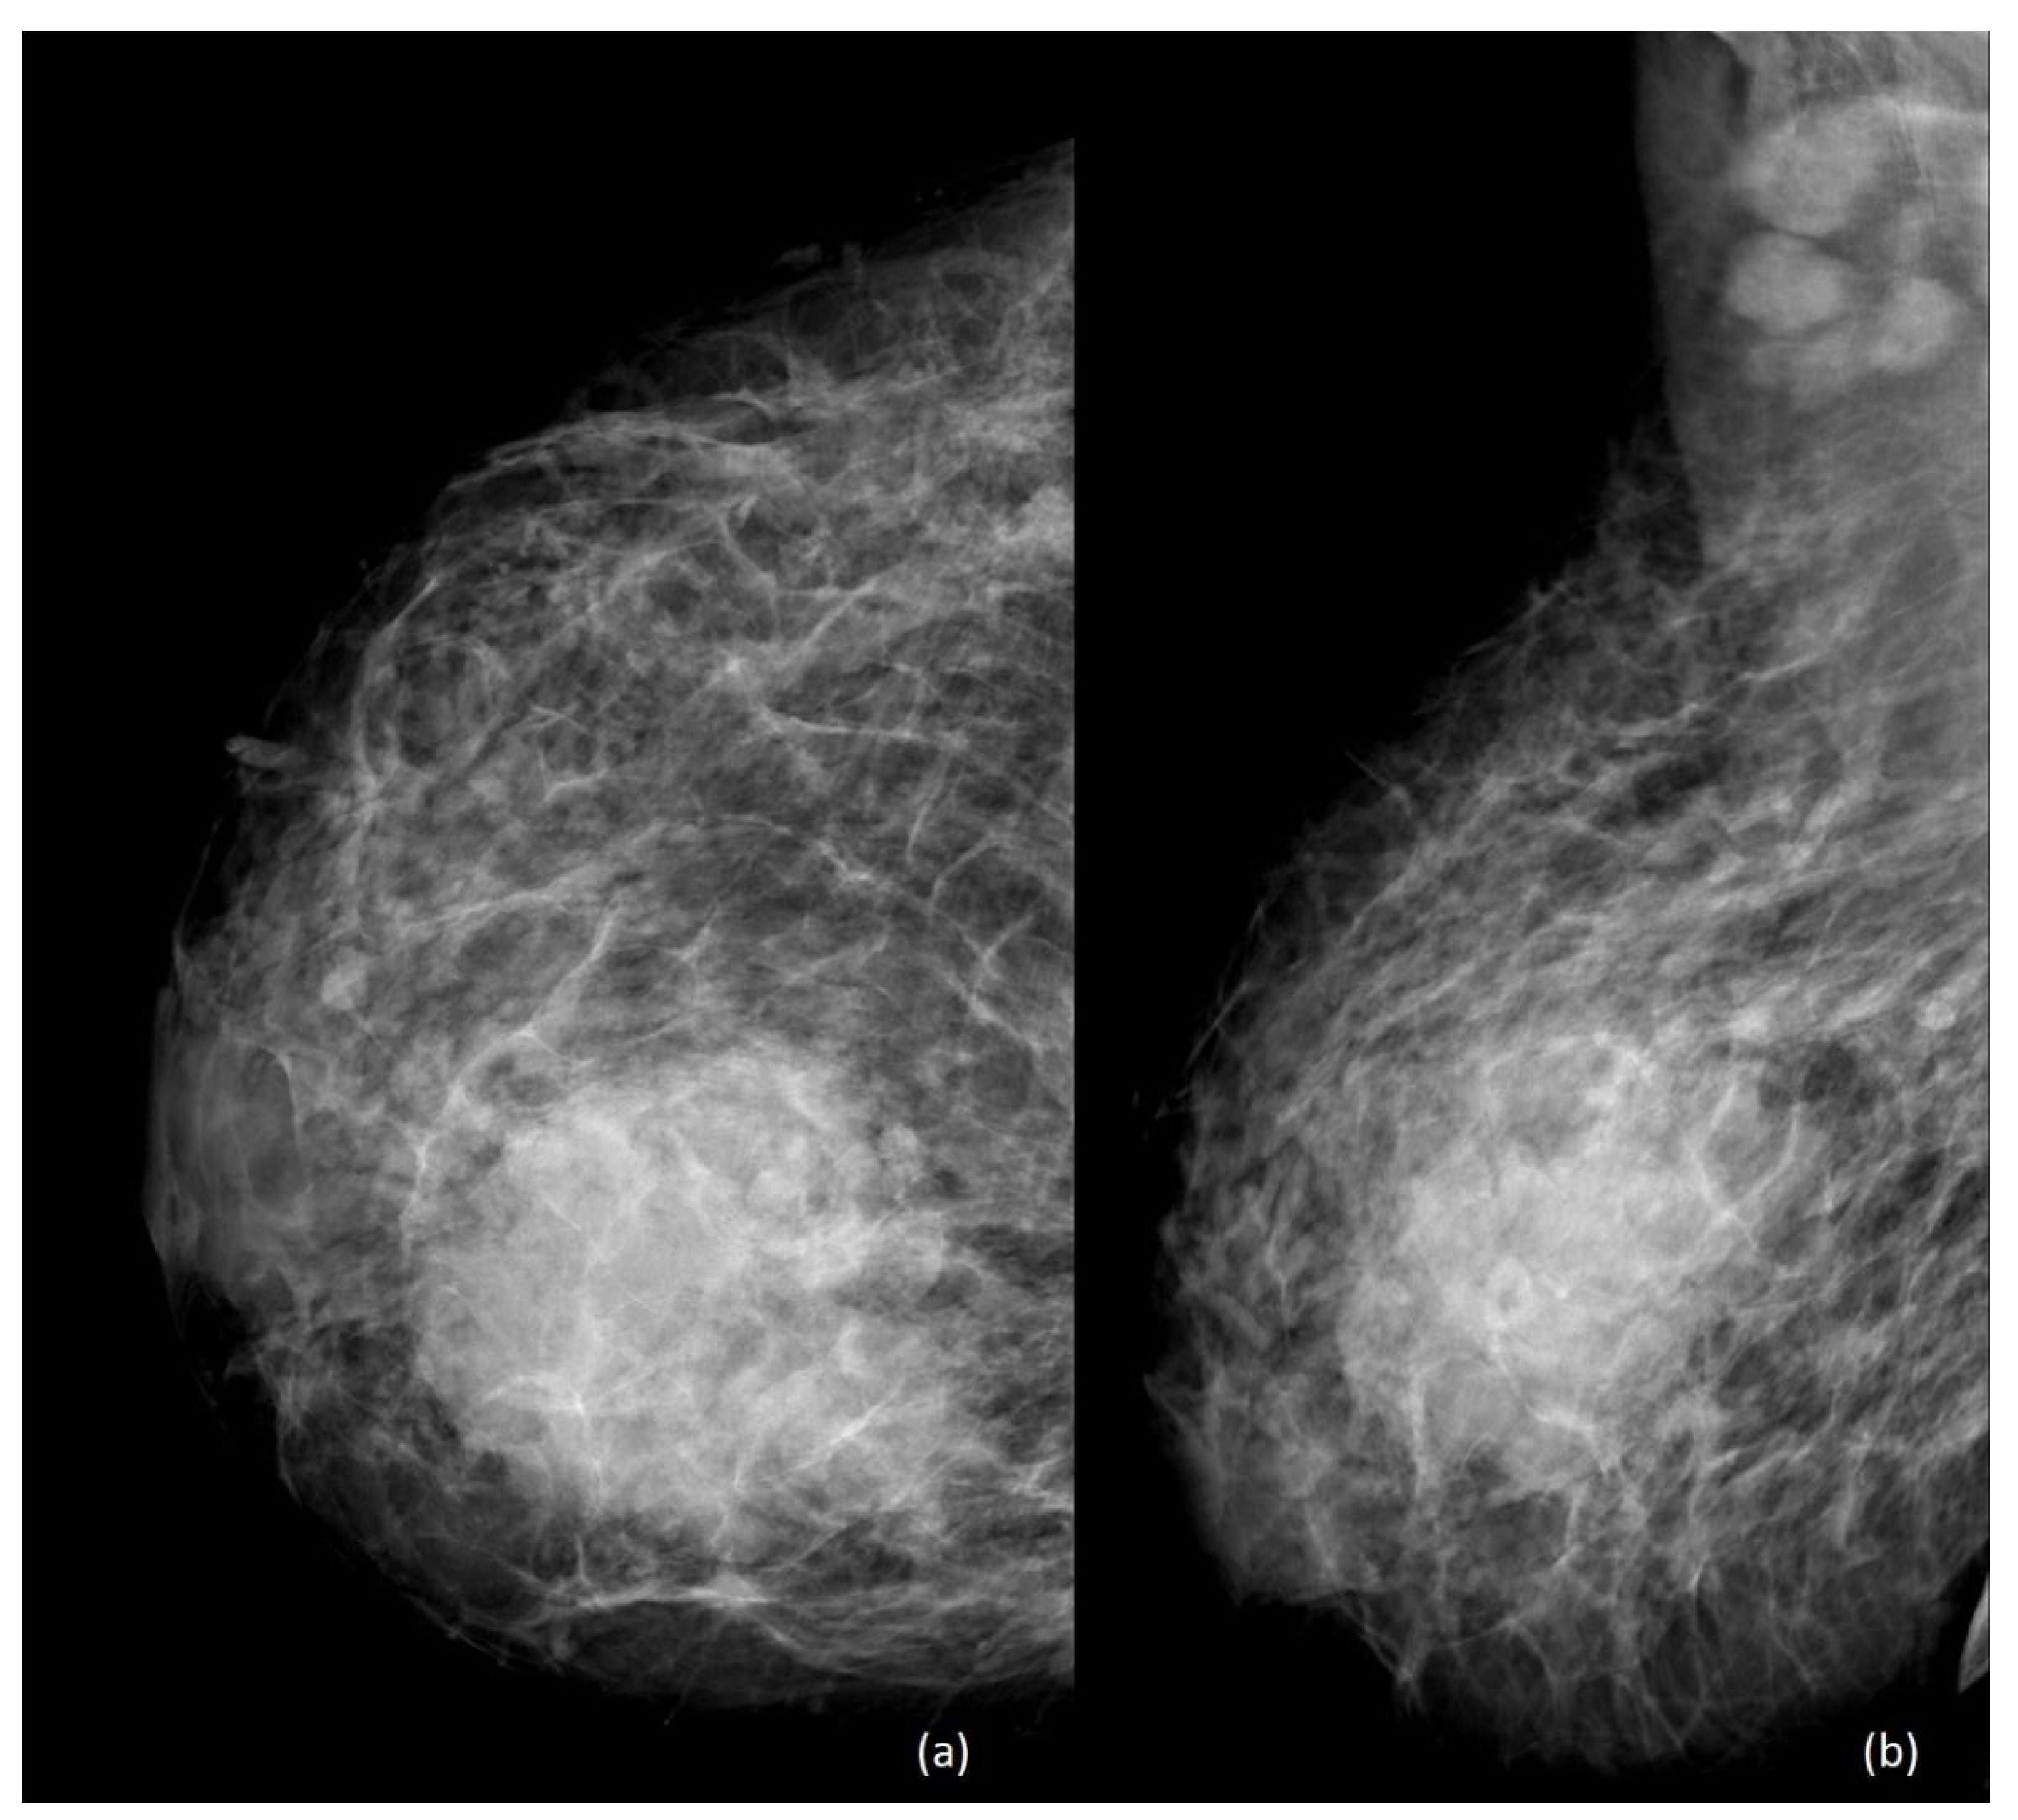

4. Imaging

- Ayyappan, A.P.; Kulkarni, S.; Crystal, P. Pregnancy-associated breast cancer: Spectrum of imaging appearances. Br. J. Radiol. 2010, 83, 529–534. [Google Scholar] [CrossRef] [PubMed]

- Wanders, J.O.; Holland, K.; Veldhuis, W.B.; Mann, R.M.; Pijnappel, R.M.; Peeters, P.H.; van Gils, C.H.; Karssemeijer, N. Volumetric breast density affects performance of digital screening mammography. Breast Cancer Res. Treat. 2017, 162, 95–103. [Google Scholar] [CrossRef] [PubMed]